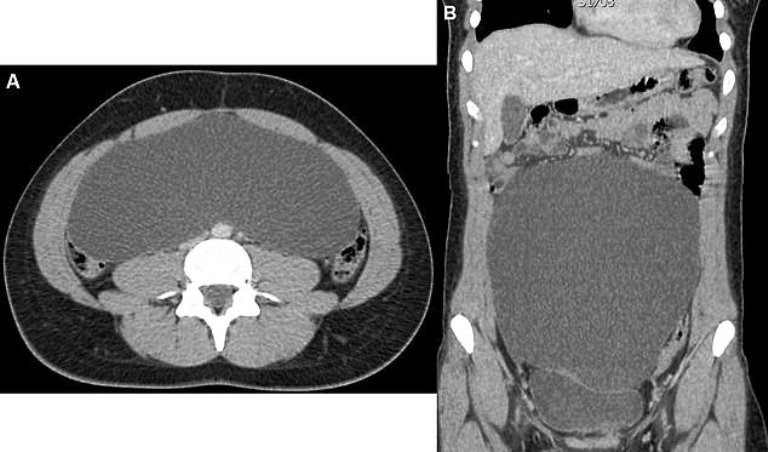

Doctors found a massive ovarian cyst so big it was ‘occupying most of her abdomen.’

The growth was not cancerous but measured 24cm by 23cm (9 1/2 inches in width and length) growing inside her.

The cause of her discomfort finally became clear when doctors performed an ultrasound scan. It showed a solid grey mass taking over most of her stomach where organs would normally be seen.